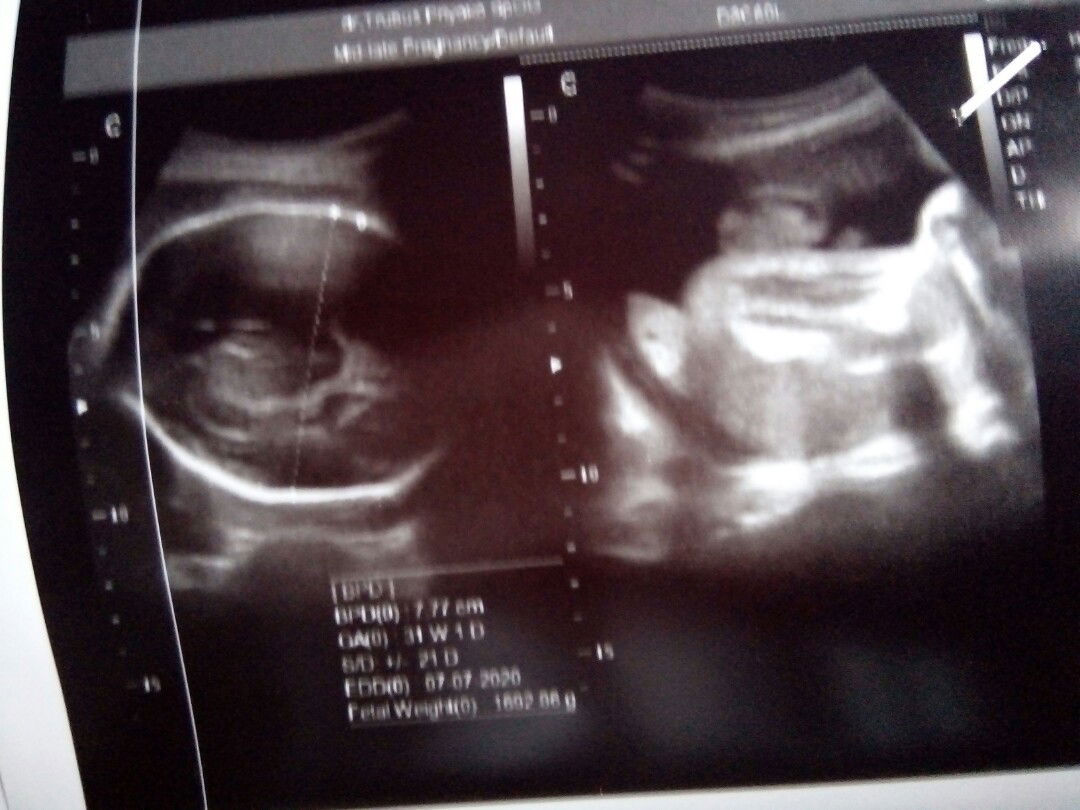

usg waktu 30 weekk

Pas liyat foto usg si dede lagi duduk atau gmna y kok pas foto usg kaya gitu